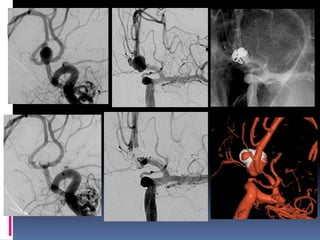

Classical blister aneurysm

34-year M, SAH

Very small aneurysms

? Near the neck rupture/lobule

Catheter reposition

1-mm coil

Branch from aneurysm-Overinflationtechnique